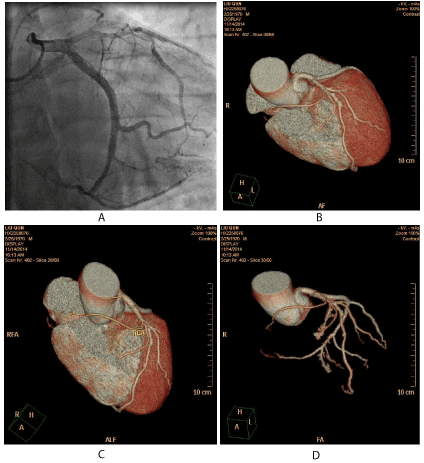

Figure 1. (A) AP caudal view demonstrates the anomalous right coronary artery originating from the distal of left circumflex coronary artery and there is severe stenosis in the proximal of anomalous right coronary artery segment. (B) Reconstructed three-dimensional image obtained by volume-rendering technique demonstrates part of the anomalous RCA course between aortic and pulmonary artery. (C) Reconstructed three-dimensional image obtained by volume-rendering technique demonstrates part of the anomalous RCA originating from the mid of the left anterior descending coronary artery. (D) Reconstructed three-dimensional image obtained by volume-rendering technique demonstrates another part of the anomalous RCA originating from the distal of the left circumflex coronary artery.

Before the coronary angiography, a 64-slice computed tomography (MSCT) of the heart was performed on a 64-slice machine (Philips 64 Slice, Philips, Netherland). The results showed the anomalous right coronary artery part originating from the mid of the left anterior descending coronary artery, and another part arising from the distal of left circumflex coronary artery (Figures 1b-1d). There was severe stenosis in the proximal of the anomalous right coronary artery. The anomalous RCA was classified as single coronary anomaly, L-I subtype.